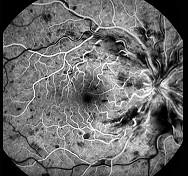

问题 该图是何种疾病的荧光造影图 ( )

选项 A、视网膜分支静脉阻塞 B、视网膜静脉周围炎 C、视网膜中央静脉阻塞 D、视网膜分支动脉阻塞 E、视网膜中央动脉阻塞

答案 C